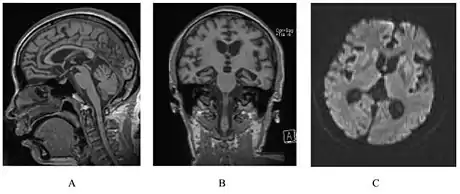

A person with inherited prion disease has cerebellar atrophy. This is typical for GSS.

A person with inherited prion disease has cerebellar atrophy. This is quite typical of GSS.